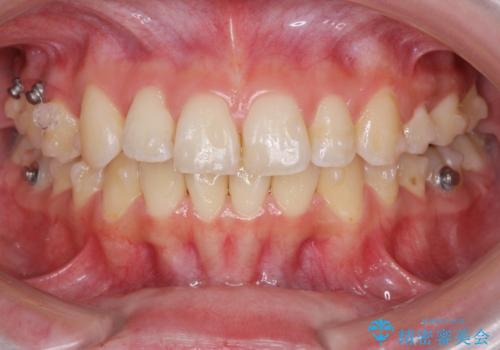

- 前歯の角度 奥歯の噛み合わせの改善をするために、矯正治療を希望され来院されました。

右側奥歯は上顎が相対的に前方に位置し(上顎前突)、そのため前歯の角度も突き出たようになり出っ歯のように見える状態でした。

マイクロインプラントを用いて、上顎奥歯を後方に移動させることで噛み合わせ・前歯の角度を改善していきます。

少し時間はかかりましたが、しっかりと綺麗な歯並びに仕上げることができ、大変喜んでいただくことができました。